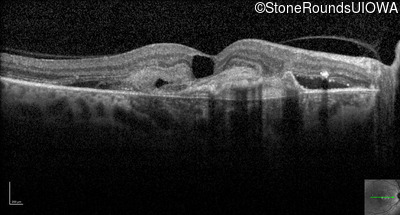

Optical Coherence Tomography - Right - 20/250

Exemplar / OCT Stack